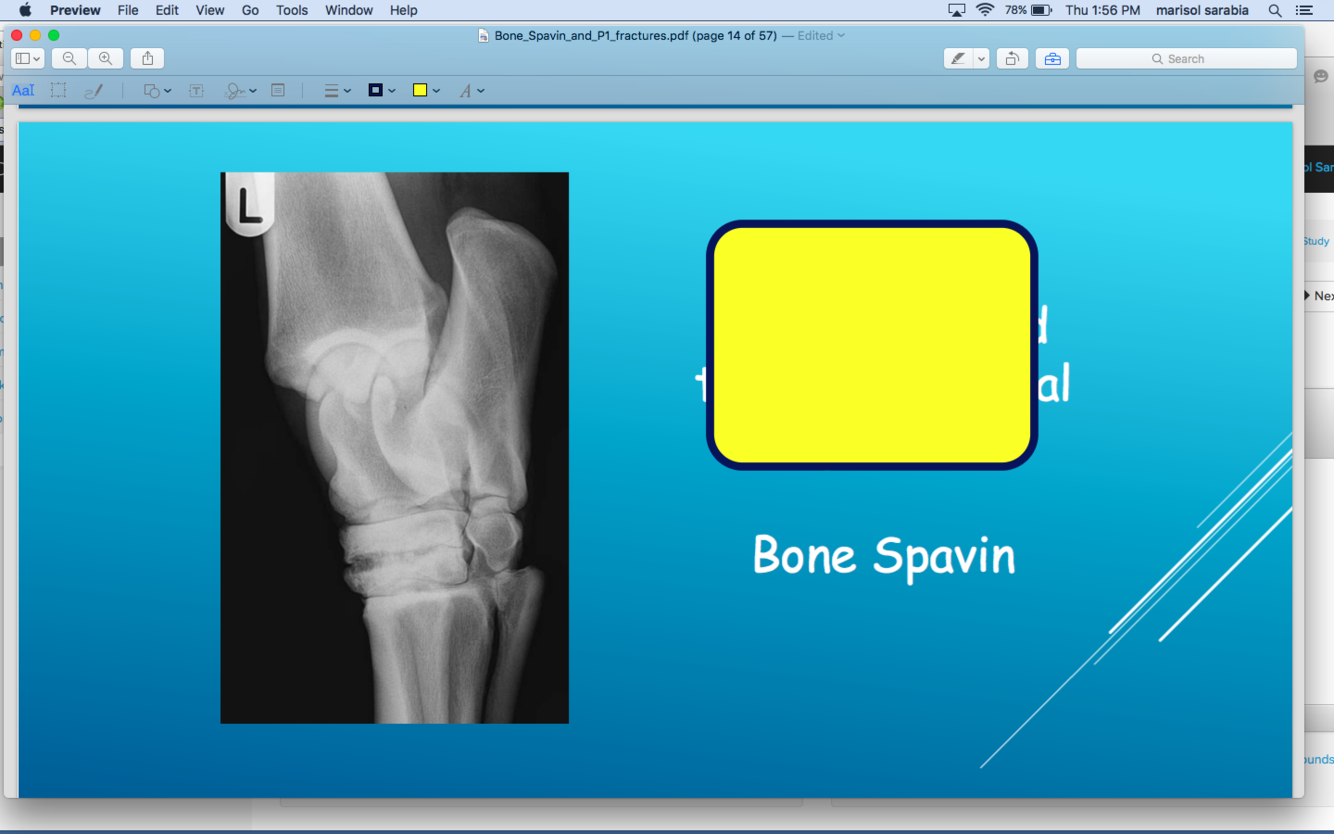

what is this a pix of

DJD of distal intertasrsal and tarso metatarsal jts